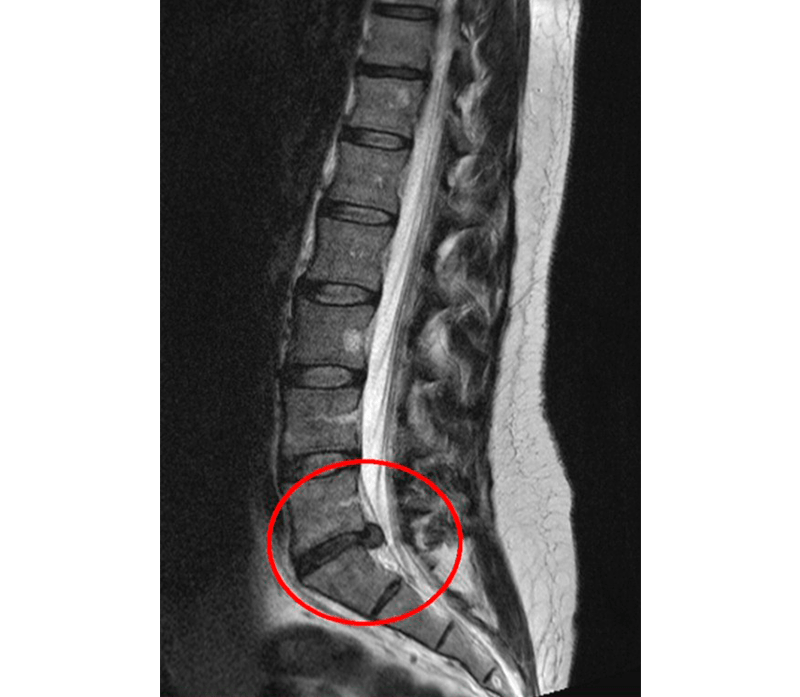

Si quieres confirmar si hay una hernia discal lo mejor es que hables con tu médico para que te solicite una

• RESONANCIA MAGNÉTICA: Que nos permite ver todos los tejidos, tanto óseos como blandos pudiéndose identificar claramente si hay una o varias hernias y la zona donde están generando irritación en caso de hacerlo.